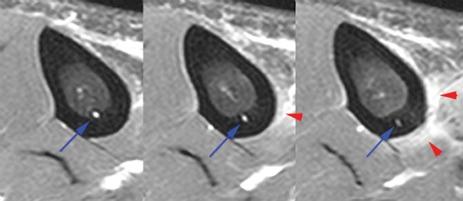

Orthopaedic magnetic resonance imaging challenge.

Bodor Daniel, Awh Mark H, Stadnick Michael E

Sports Health. 2010 Jul;2(4):351-5. doi: 10.1177/1941738110373452.